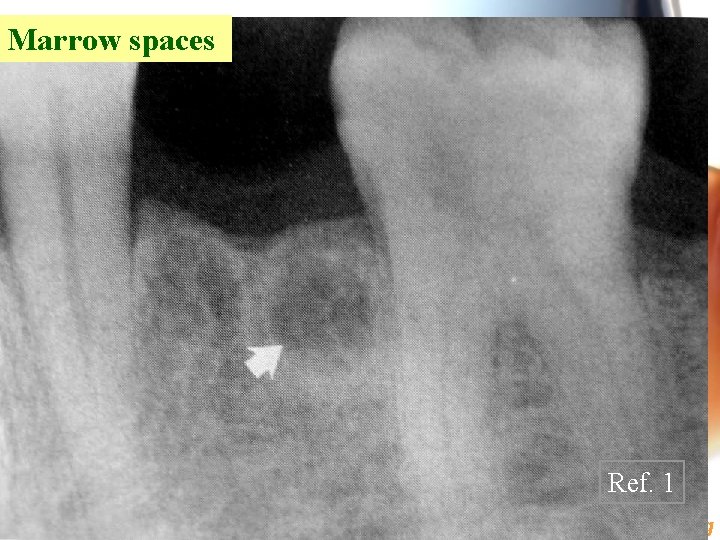

Marrow spaces Ref. 1 Wen. Chen Wang